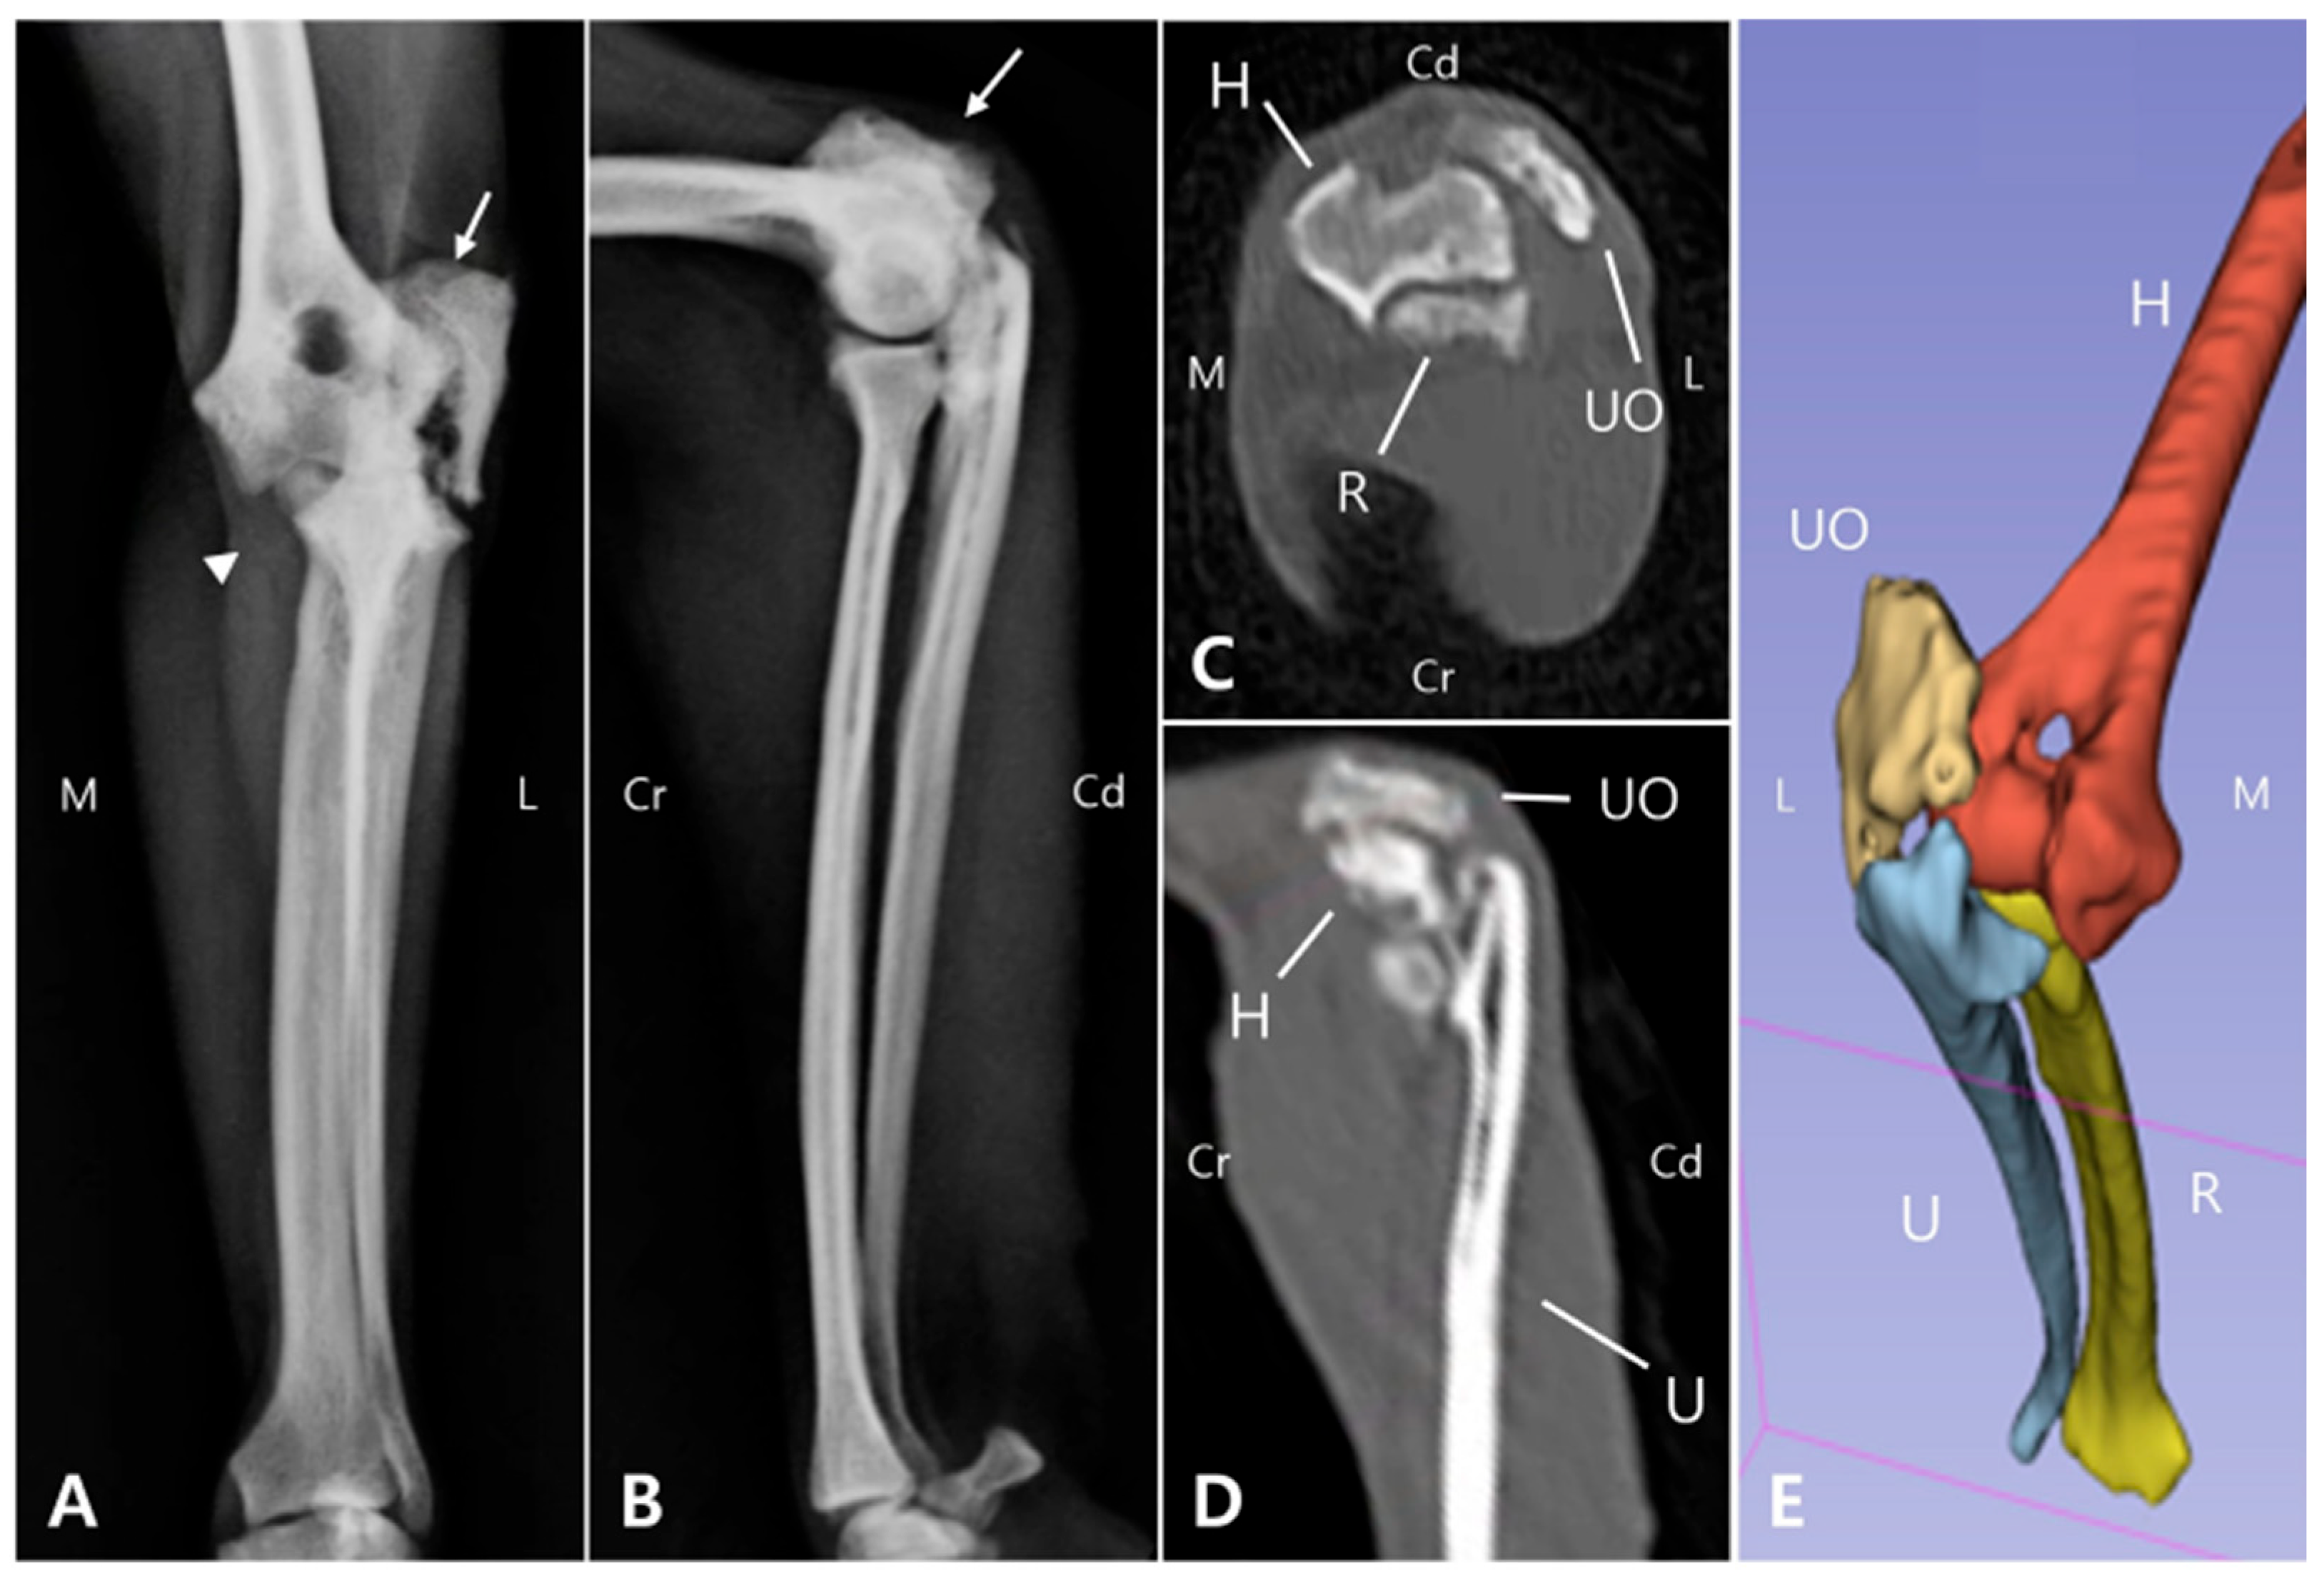

Radiographic and computed tomography (CT) imaging were obtained, revealing a fracture involving the olecranon of the left ulna, with ill-defined fracture margins and ulna luxation, while radiocapitellar alignment remained preserved. Additionally, sclerosis, osteolysis, deformation, and craniolateral displacement of the olecranon were observed. Sclerosis was also observed at the proximal diaphysis of the left ulna, with a well-defined, linear 3.0 mm bone fragment located caudally (Figure 1A,B). Soft tissue width was assessed on lateral radiographs by measuring soft tissue thickness at the midshaft of the humerus (brachium) and at the proximal one-third of the radius (antebrachium). In the right forelimb, the soft tissue width measured 48.69 mm at the brachium and 28.53 mm at the antebrachium, whereas in the left forelimb, the corresponding measurements were 32.25 mm and 21.04 mm, respectively. The values of the affected limb corresponded to 66.2% (brachium) and 73.7% (antebrachium) of those of the contralateral side. These results were consistent with the circumferential measurements and indicated muscle atrophy in the affected limb compared with the contralateral side. These findings indicated moderate muscle atrophy in the left forelimb compared to the contralateral side. Due to the chronic nature of injury, the fracture and luxation led to fibrosis of the surrounding joint tissues and chronic arthritis (Figure 1C,D), making it challenging to clearly identify the fracture anatomy and localization, which was important for surgical planning. Therefore, 3D modeling and printing were utilized to enable more precise preoperative planning.

2.3. Presurgical Plannings

To develop a surgical plan for olecranon fracture repair and joint reconstruction, 3D models were reconstructed from CT Digital Imaging and Communications in Medicine (DICOM) files using 3D Slicer 5.2.2 (Brigham and Women’s Hospital, Boston, MA, USA) (Figure 1E). The fractured olecranon and luxated elbow joint were then modeled using 3ds Max (Autodesk, San Francisco, CA, USA). Both the fractured and simulated repaired bone models were 3D printed using UV Tough resin and a 3D printer (Anycubic Photon M3 Max, Shenzhen Anycubic Technology Co., Ltd., Shenzhen, China) [20,21].

Figure 1. Preoperative radiographic, CT, and 3D reconstruction regarding the left elbow joint. On the anteroposterior radiograph (A), an olecranon fracture (arrow) and apparent dislocation of medial coronoid process (arrowhead) are evident. On the medio-lateral radiograph (B), the olecranon is displaced proximally (arrow), likely due to traction exerted by the triceps muscle. These images demonstrate a left olecranon fracture with associated ulnohumeral luxation. In the coronal and sagittal CT planes (C and D, respectively), periarticular fibrosis together with soft tissue proliferation at the fracture site impeded precise delineation of the fracture anatomy and localization. The 3D model (E) reconstructed from the CT data provides a clear structural depiction of the olecranon fracture and ulnar luxation. (M: Medial, L: Lateral, Cr: Cranial, Cd: Caudal, UO: Ulna olecranon, H: Humerus, U: Ulna, R: Radius).